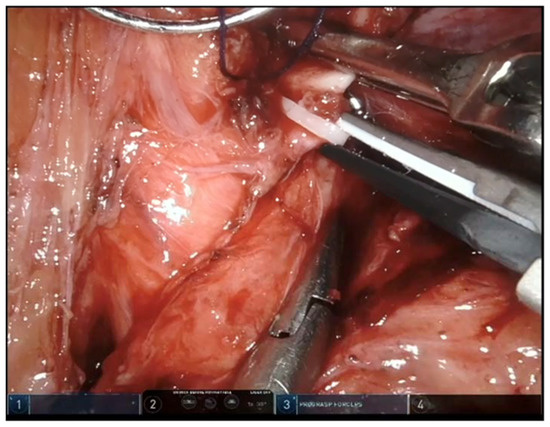

3.1. Case #1: Timely Recognition of SMA Misidentification

3.2. Case #2: SMA Clipping

3.3. Case #3: SMA Clipping and Complete Transection